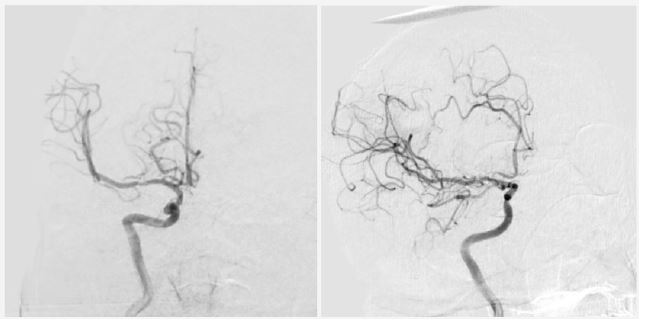

Twenty-four hours post-admission, his neurological status worsened (GCS decreased by 4 points), and a CT scan showed a significant midline shift. A right-sided frontotemporoparietal decompressive craniectomy was performed. Postoperatively, his GCS improved to 14 and motor strength improved to 3/5 on the Lovett scale (Figure 2). A Computed Tomography Angiography (CTA) performed 48 hours after surgery showed restored flow in the M1 and distal branches of the right MCA (Figure 3). A confirmatory cerebral angiogram at two weeks demonstrated patent flow throughout the MCA distribution (Figure 4).

Figure 2: Post-decompressive craniectomy computed tomography. Evidence of persistent ischemia is observed in the right MCA territory.

Figure 3: Computed tomography angiography 48 hours after decompressive craniectomy, showing vascular flow in the right MCA territory.

Figure 4: Cerebral angiography 2 weeks later, showing recanalization of the right MCA.